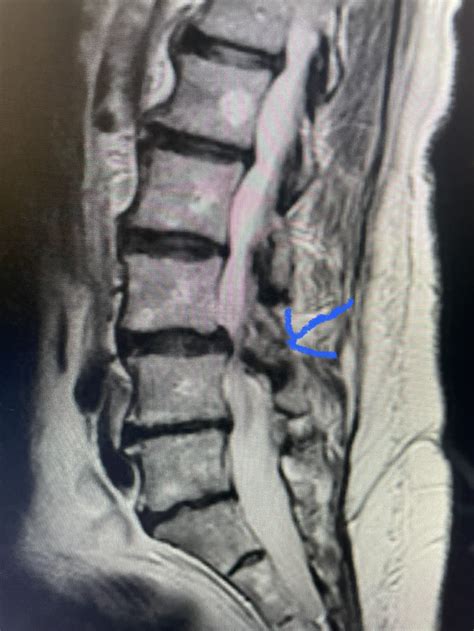

• Imaging studies: Diagnostic imaging, such as X-rays, MRI, or CT scans, can provide detailed images of the spine and identify the thickening of the ligamentum flavum.

Imaging studies are particularly important in confirming the diagnosis and determining the extent of the condition.